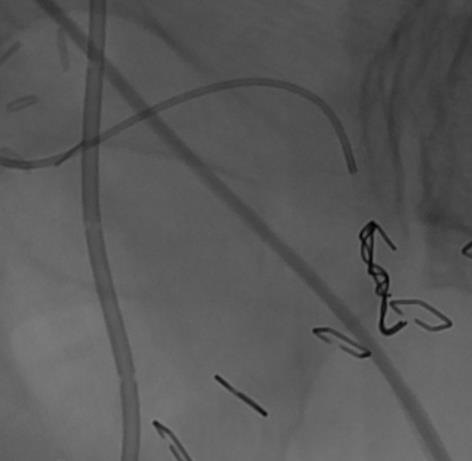

外伤后出血的栓塞

外伤后可见造影剂外溢 |

微导管选择至出血血管 |

出血血管的微弹簧栓子栓塞 |

栓塞后造影 |